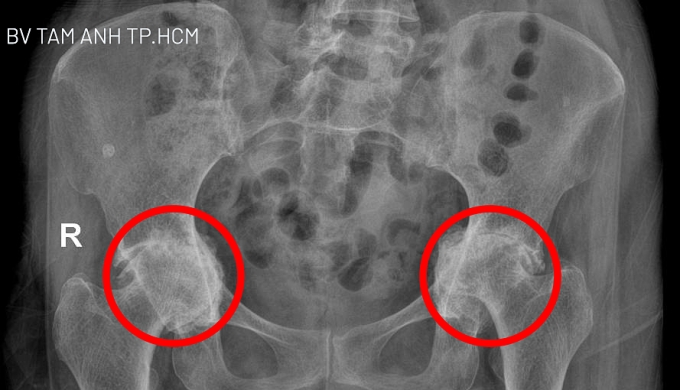

Trước đó, chị San Samphors điều trị bằng thuốc ở bệnh viện tại Campuchia, Thái Lan không khỏi, gần đây đau nặng hơn. Kết quả chụp X-quang tại Bệnh viện Đa khoa Tâm Anh TP HCM cho thấy sụn ở hai bên khớp gối của người bệnh bị mài mòn hoàn toàn và tiêu biến. Khớp háng hai chân thoái hóa nặng, chỏm xương đùi lệch khỏi vị trí bình thường, chui vào trong ổ bụng. Bác sĩ Khoa nhận định đây là trường hợp rất nặng, phẫu thuật là phương pháp duy nhất giải phóng người bệnh khỏi đau đớn và khôi phục khả năng vận động.

Kết quả chụp X-quang cho thấy khớp háng hai bên phá vỡ khung chậu và đang dần “chui” vào ổ bụng. Ảnh: Bệnh viện Đa khoa Tâm Anh